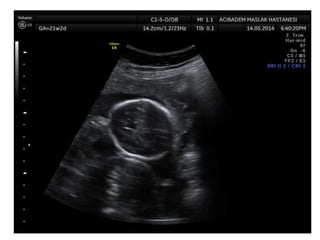

Arthrogryposis

•Multiple congenital joint contractures/ankyloses

involving two or more body areas

•Pena Shokeir phenotype

micrognathia, multiple contractures, camptodactyly

(persistent finger flexion), polyhydramnios

*many are AR

*Lethal due to pulmonary hypoplasia

• Distal arthrogryposis

Subset of non-progressive contractures w/o associated

primary neurologic or muscle disease